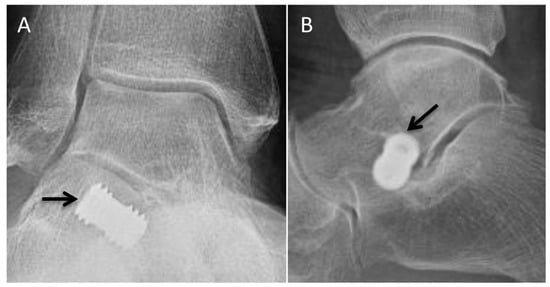

5.1. Polyvinyl Alcohol Hydrogel Hemiarthroplasty/Synthetic Cartilage Implant (SCI)

5.2. Silastic Implant